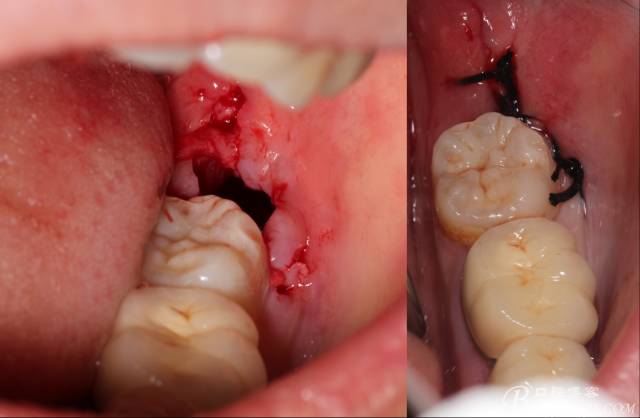

分冠完成

640 (12).jpg

取出阻力部分冠

640 (13).jpg

在取出阻力冠后,嘗試性看能取出全部的牙體不,就是取不出也能整體撬動(dòng)牙根。

計(jì)劃總趕不上變化,何況是充滿變異的智齒。由于可操作空間較小,原來計(jì)劃橫向分根改成矢狀分根。

現(xiàn)在都在提倡微創(chuàng),個(gè)人看法微創(chuàng)是相對(duì),所當(dāng)然微創(chuàng)是我們的追求。完全撥出,縫合關(guān)閉創(chuàng)口,常規(guī)智齒撥除醫(yī)囑,不適隨診。